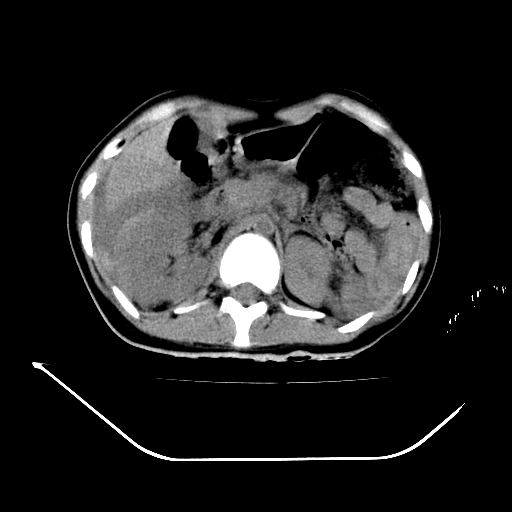

以下是引用liuyue在2008-7-19 13:02:00的发言:[br]1.肝右叶后下段及右肾挫裂伤伴腹腔积血。[br]2.右侧多发性肋骨骨折、横突骨折、右髂骨骨折伴周围软组织挫伤。[br]3.右侧腰大肌肿胀,并可见低密度影,如为气体,则肠道挫裂伤待除外。

以下是引用zhengfaming在2008-7-19 14:42:00的发言:[br]1.肝右叶后下段及右肾挫裂伤伴腹腔积血。脾脏挫裂伤待排[br]2.右侧多发性肋骨骨折、横突骨折、右髂骨骨折伴周围软组织挫伤。[br]3.右侧腰大肌肿胀,并可见低密度影,如为气体,则肠道挫裂伤待除外

以下是引用道哥在2008-7-19 16:52:00的发言:[br]肝右叶后下段及右肾挫裂伤、脾破裂伴腹腔积血。[br]2.双侧多发性肋骨骨折、横突骨折、右髂骨骨折伴周围软组织挫伤。[br]3.右侧腰大肌肿胀,并可见低密度影,如为气体,则肠道挫裂伤待除外。